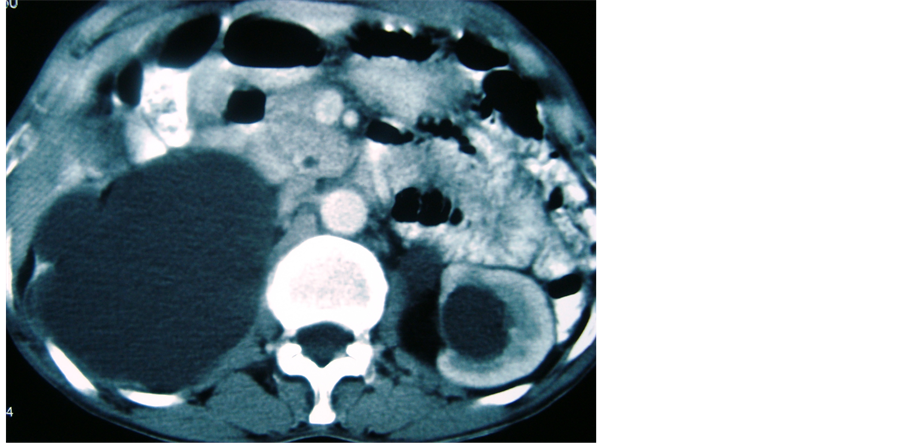

A 50 year male presented with retention of urine for the last one day. He gave past history of difficulty in micturition for last five years along with pain in right loin for last six months. Examination revealed a firm, smooth, non mobile and non tender mass in suprapubic region along with a ballotable mass in right lumbar region. On per rectal examination, a smooth cystic mass was felt anteriorly in the rectovesical pouch. Serum creatinine, urea and electrolytes, liver function test and urine analysis were normal. Ultrasound examination revealed a cystic mass in pelvis suggestive of a hydatid cyst with bilateral hydronephrosis. There was no lesion in the liver. Computerized tomography (CT) scan revealed a pelvic hydatid cyst with bilateral hydronephrosis with non functioning right kidney (Figure 1, Figure 2). Indirect haemagglutination test for hydatid disease was negative.

Figure 2. Showing bilateral hydronephrosis.